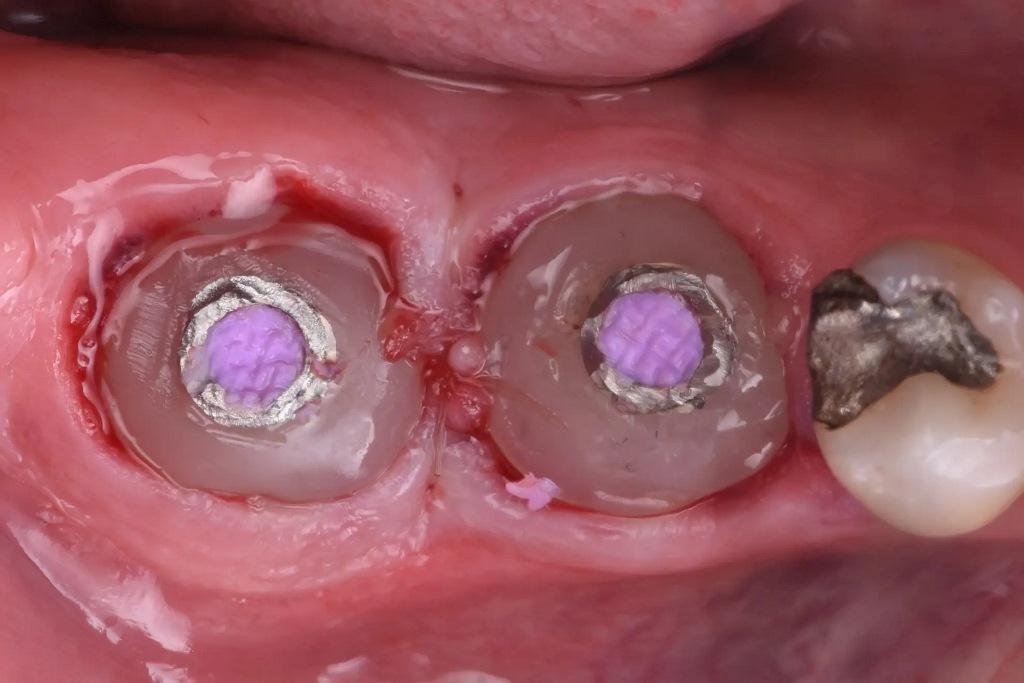

Были изготовлены индивидуальные заживляющие абатменты с использованием временного абатмента и композита, отполированы до высокого блеска с помощью силиконовых шлифовальных кругов, а затем установлены (фото 11). Пациенту были даны стандартные послеоперационные инструкции для поддержания заживления операционного поля в течение последующих месяцев.

Фото 11: Специальные заживляющие абатменты установлены.